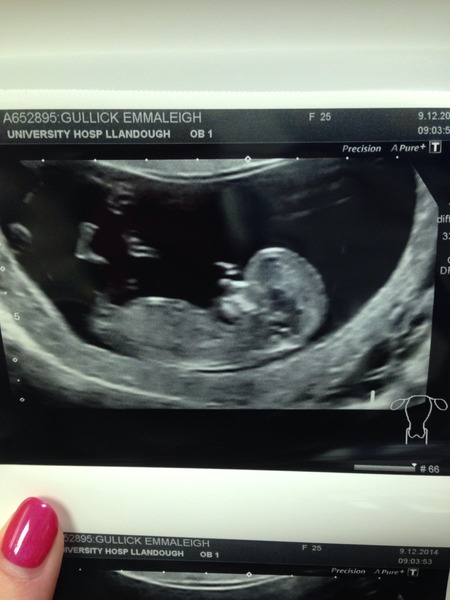

Hello all, really pleased to be able to attach a photo of my bouncing bean! Very wriggly and bouncy, sonographer took a while to do all her measurements because bean wouldn't get into the right position!! Measured 11+5 so edd is June 25th. Thanks for your kind words and wishes this morning!

Lovely pic Emz - many congrats (and very glam nails too!)

Just to warn you that your name is very visible on the scan when you click on the pic. You might be fine with that but I thought I'd let you know.

Congrats emz lovely pic! That little foot!